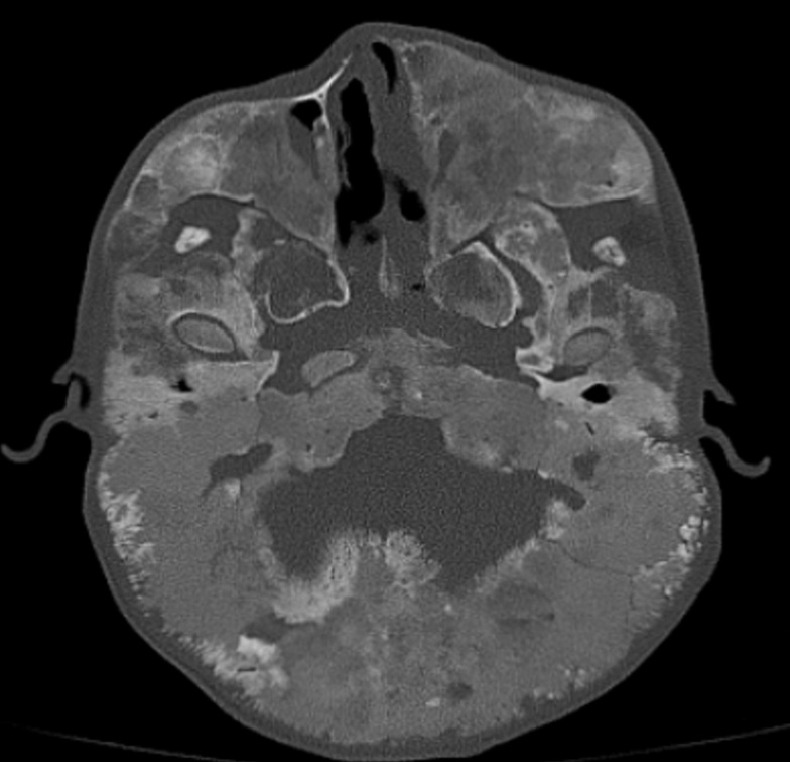

Endoscopic endonasal transsphenoidal approach of pituitary macroadenoma and optic canal stenosis in a patient with McCune-Albright syndrome.

Abstract Image